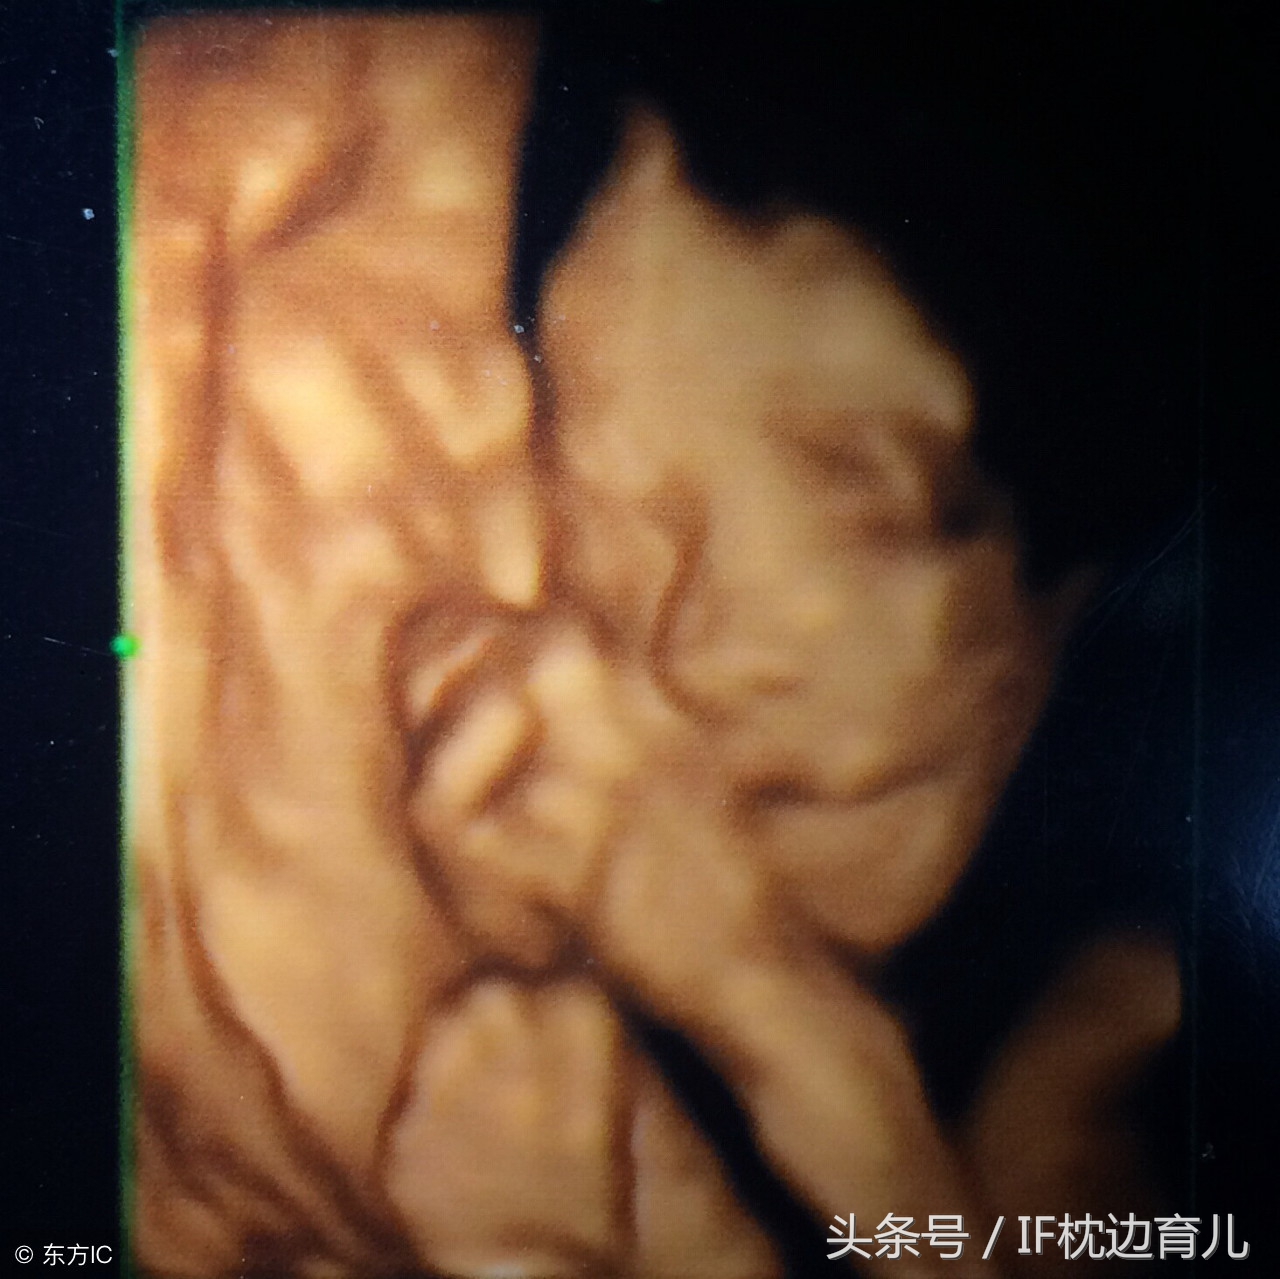

乐乐怀孕6个月了,这周要去做四维检查了,她和老公两个人准备产检时做个照片留念,看看宝宝出生后跟在肚子里有什么区别?可是检查时,乐乐和老公在看到检查仪器上的胎儿时,不禁嫌弃起来:我和老公长相都算中上等,这宝宝怎么看着“嘴大鼻子大”,生下来会不会很丑啊?一旁的医生给出这样的回答。

胎儿在子宫里有羊水、胎膜、妈妈腹壁的隔绝,通过超声而形成的影像是跟实际有偏差的。而且,怀孕六个月时,胎儿脑部发育趋近完善,但是身体脂肪堆积还未形成,胎儿脸部肌肉比较少,所以会显得鼻子和嘴巴比较大。在做检查时需要放大看胎儿的面部,检查有无明显体表畸形。所以会出现大头照,显得胎儿“嘴大鼻子大”。用白话说就是,子宫空间那么小,胎儿面部会受到挤压,再加上检查时需要仔细观察,放大影像。出现这种情况也就很正常了。乐乐和老公听的似懂非懂,不过,既然医生这么说,表示胎儿很健康就对了。

所以当6个月做四维检查时,妈妈们看到胎儿“嘴巴鼻子比较大”,属于正常现象,也符合胎儿发育变化,等宝宝出生后,像个皱巴巴的“小老头”,一般满月后,就长开了,也会越长越好看。